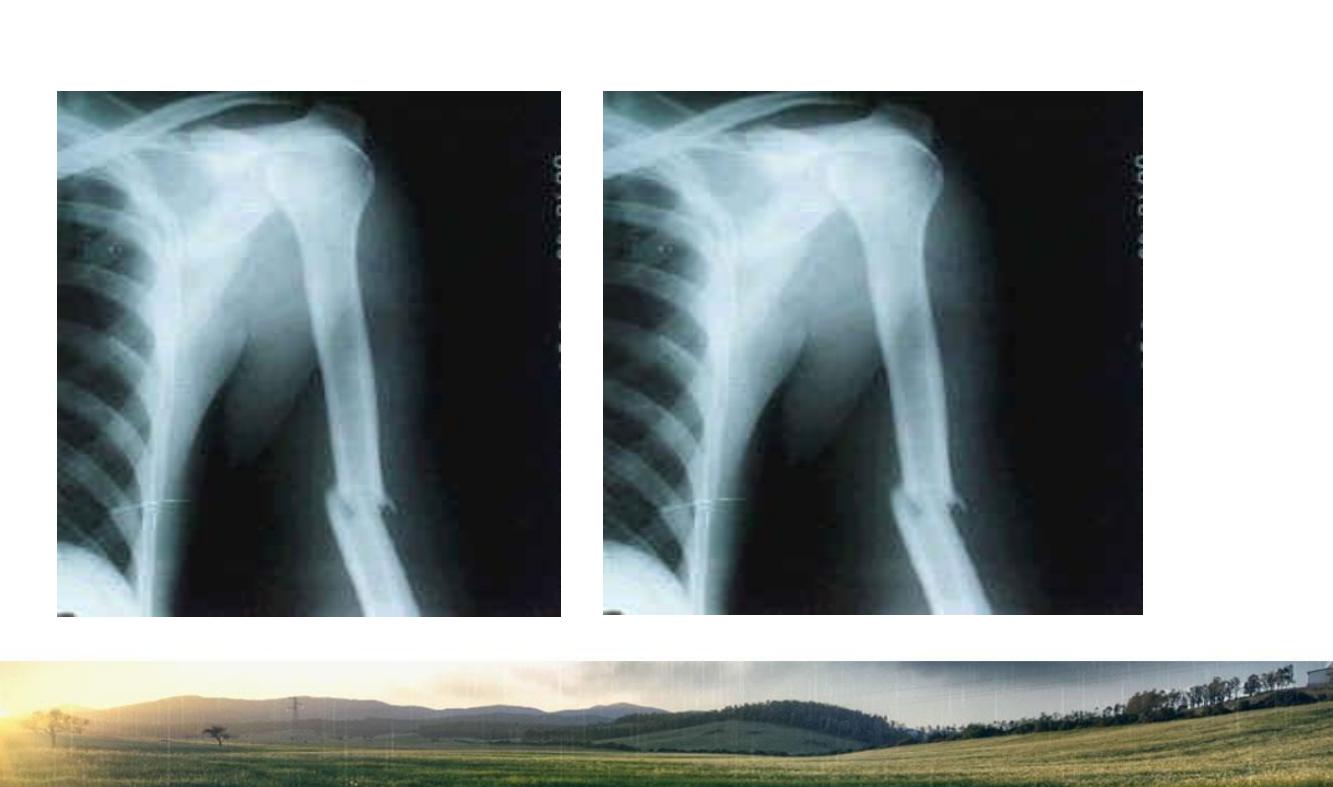

肱骨干骨折的临床治疗